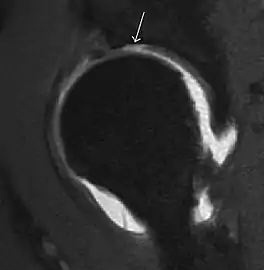

Synovial chondromatosis can be confidently diagnosed by X-ray when calcified cartilaginous chondromas are seen. However, other synovial proliferative processes, such as pigmented villonodular synovitis, require MRI for accurate diagnosis, although noncalcified synovitis can be suspected in radiographs by indirect signs, such as soft tissue swelling and/or erosions in the femoral head, femoral neck, or acetabulum (Figure 7).[1]

Figure 7:

- Axial CT image of pigmented villonodular synovitis eroding the posterior cortex of the femoral neck.[1]

- Sagittal T2* gradient echo image showing a posterior soft tissue mass with hypointense areas secondary to hemosiderin deposition.[1]

In synovial proliferative disorders, MRI demonstrates synovial hypertrophy. In the case of PVNS, characteristic foci of low signal intensity related to hemosiderin deposition are better seen on gradient echo T2* images (Figure 7). In the case of synovial osteochondromatosis, the synovial hypertrophy is accompanied by intermediate signal cartilaginous loose bodies and/or low signal calcified loose bodies.[1]